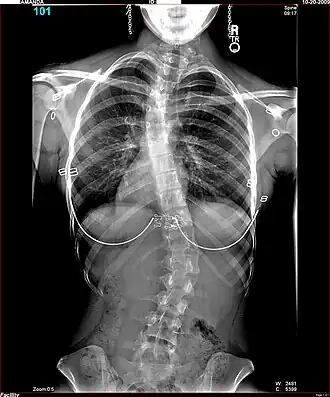

Men onderscheidt een S-vormige scoliose met twee bochten en een C-vormige scoliose met één bocht. Een S-scoliose benoemt men naar de convexe (bolle) kant van de grootste bocht; bijvoorbeeld een S-vormige thoracale scoliose, rechts convex van 35 graden. De wervelkolom is meestal tevens om zijn as gedraaid, men spreekt dan van een torsiescoliose, waardoor een bochel (gibbus) ontstaat. Hoewel het een ingewikkelde driedimensionale vervorming betreft, kan men op een gewone voor-achterwaartse röntgenfoto de zijdelingse verkromming goed zien als een C-vormige of een S-vormige slinger in de ruggengraat die eigenlijk een rechte lijn behoort te zijn. Een structurele scoliose zal meestal gepaard gaan met een draaiing, een torsie; ook een bijkomende voorovergebogen houding (kyfose), een holle rug (lordose) of beide komen vaak samen met de scoliose voor. Belangrijk is of de scoliose in evenwicht is, dat wil zeggen of het zwaartepunt van het lichaam tussen de voeten valt. Als de wervelkolom van de patiënt een S-vormige bocht heeft, kan zich op borsthoogte een convexe bocht naar rechts bevinden en op lendenniveau een convexe bocht naar links. Meestal heffen de bochten elkaar op. Indien dit niet het geval is, bestaat er een grote kans op verergering.

Voor operatie